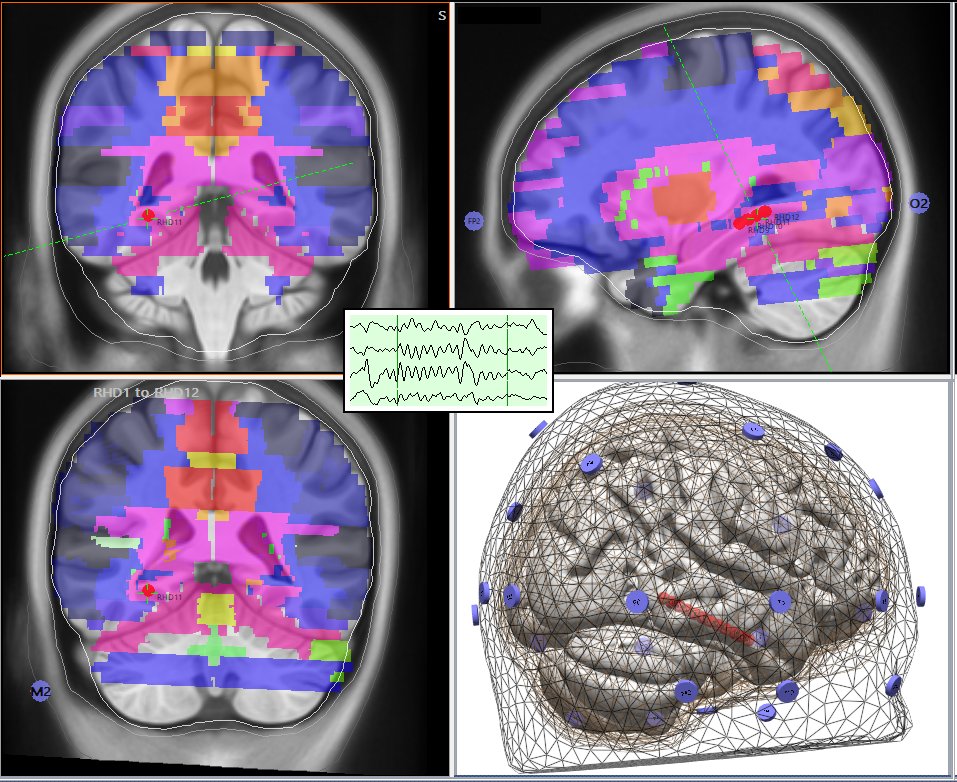

Researchers scanned his brain and made a chilling discovery:

He wasn’t *fully* awake

Parts of his brain were asleep

Literally shutting down

One region at a time

While his eyes stayed open

They called it: **microsleep**

Your brain sleeping in bursts Image